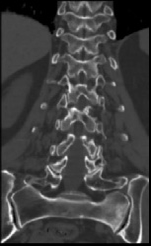

开展的CT检查项目有:全身 CT平扫和增强 检查(含头颅、颈部、胸部、腹部、盆腔、骨关节,四肢等)。

特色项目:(1)CT下肢动脉血管成像(CTA);通过增强血管成像,可清楚显示并明确动脉血管病变范围、程度和性质,如下肢动脉狭窄,闭塞等。(2)心脏冠状动脉CTA:通过增强检查,可显示多种心脏疾病,分析冠脉斑块成分及狭窄程度。(3)CT定位下穿刺活检:在CT引导下对病变部位进行穿刺,取病变组织用于病理检查,明显病变性质。常用于胸部、肝脏、肾脏、骨骼等部位。